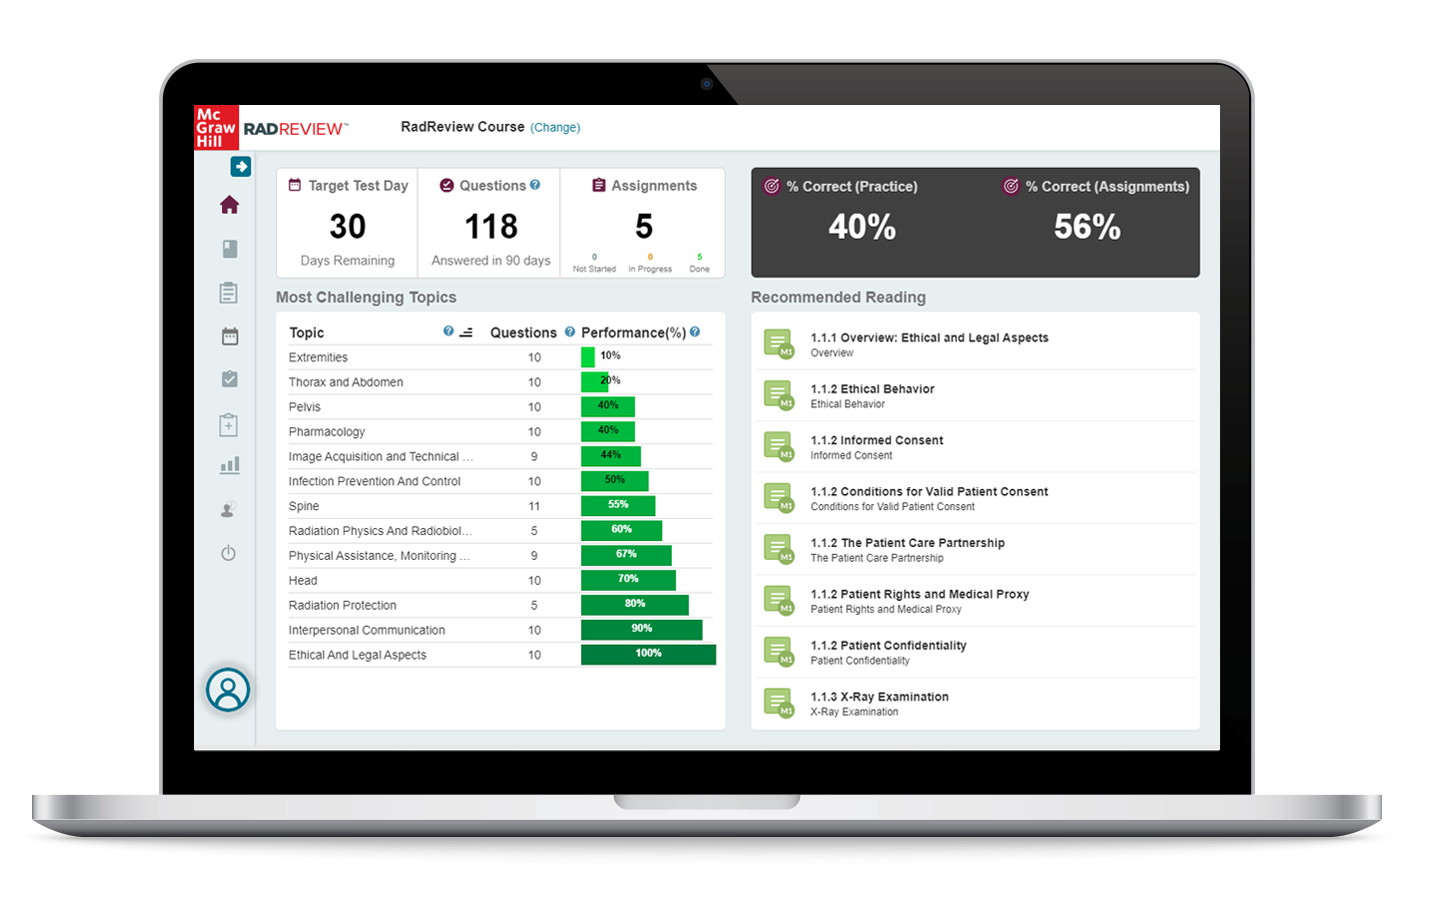

Rad Tech Exam Paid Performance Tracking Tests, Preparing for a radiologic technology (rad tech) exam can be challenging, especially with the high standards required for certification and licensure. One of the most effective modern study tools available to students today …

Rad Tech Exam Paid Evaluation Tests, Becoming a certified radiologic technologist is a significant achievement, but passing the certification exam can be challenging. The exam covers a wide range of topics, from patient care and radiation safety to image production …

Rad Tech Exam Simulation Software Buy, Becoming a certified radiologic technologist requires dedication, hands-on training, and thorough exam preparation. One of the most effective modern tools for success is exam simulation software. Many students and professionals now choose to rad …